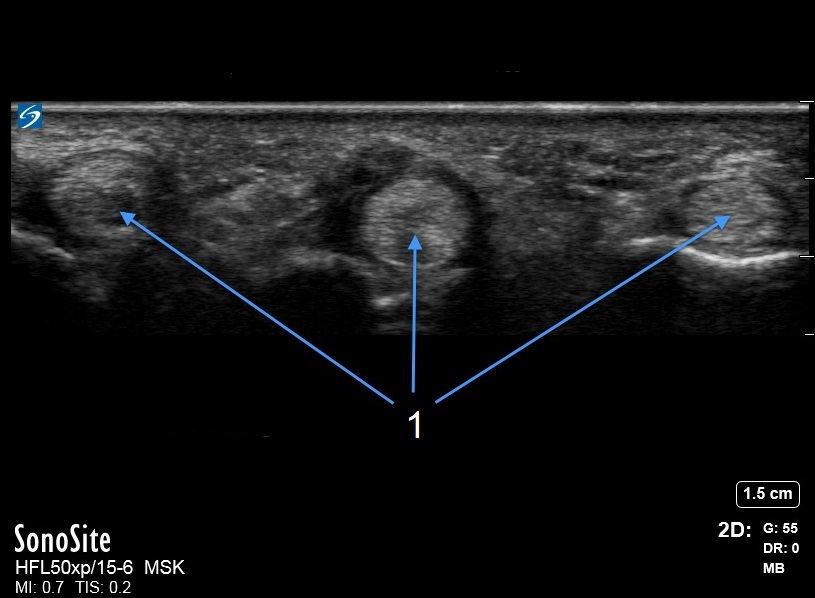

Hand Abnormal A1 Pulley Image

Flexor Tendon Transverse